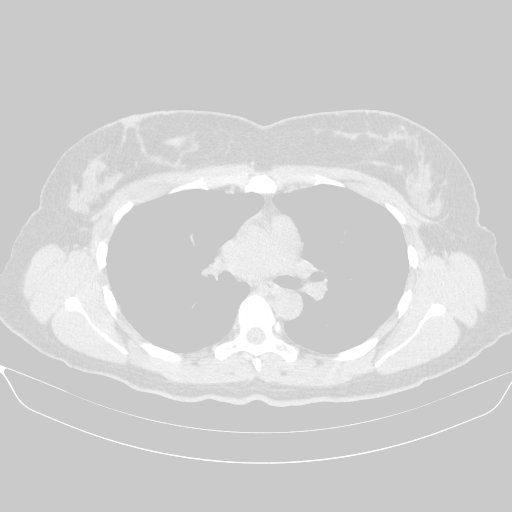

Original NATIVE CT scan (input)

No window - Raw intensity values

Lung window (WL -600, WW 1500 β†’ Low βˆ’1350, High +150)

Mediastinum window (WL 40, WW 400 β†’ Low βˆ’160, High +240)